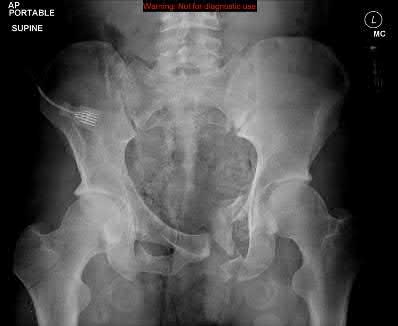

A 35 year-old female presents after prolonged extrication from a motor vehicle collision complaining of severe pelvic pain. Physical examination reveals diminished perianal sensation. She is otherwise neurologically intact. Figures A through D are radiographs and representative CT cuts of her injury. Which of the following nerve roots has likely been injured by the acute trauma?

The clinical scenario is consistent with a high-energy sacral fracture. The radiographs in figures A and B demonstrate a sacral fracture with posterior displacement of the right hemipelvis seen on the inlet view. Figures C and D are axial and sagittal CT images which show a displaced fracture of the right

hemisacrum along with a transvere fracture component through the S3 body . Diminished perianal sensation is concerning for an S2 nerve root injury.

Mehta et al reviewed the current management of sacral fractures. They note that the S1 and S2 nerve roots are more likely to be injured with sacral fractures as they occupy 1/3 to 1/4 of the neural foramina, as opposed to S3 and S4, which only occupy 1/6 of the neural foramina.

Robles reviewed the current literature to ascertain principles of evaluation and treatment for transverse sacral fractures. The author notes that injury to nerve roots S2 to S5 is manifested by impairment of urinary and anal continence and sexual function.

The first illustration demonstrates the sacral nerve root dermatomal distribution. The second shows a pelvic cadaver dissection demonstrating the sacral nerve roots as they exit the foramina.